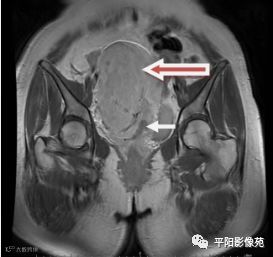

(宫腔内见金属节育环伪影)宫颈区见不规则形等T1稍长T2信号软组织肿块,DWI序列呈明显高信号,大小约为3.87cmX2.64cm,双侧宫颈基质低信号环连续性中断,病灶向子宫右后上方生长,周围脂肪间隙模糊,增强扫描明显强化,强化程度低于子宫及宫颈实质;子宫后方、子宫直肠间隙见不规则形长T1长T2信号软组织肿块,DWI序列呈高信号,大小约10.12cmX4.82cmX10.29cm,病灶呈分叶状,向下方生长与宫颈分界不清,与直肠分界尚清,增强扫描明显不均匀强化。

1.宫颈癌(T1b1N0Mx)

2.子宫后方、子宫直肠间隙占位,考虑来源于间叶组织肿瘤可能性大